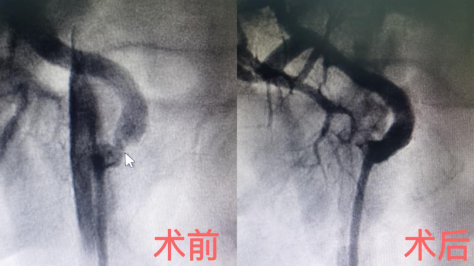

鼠标箭头指向的是术前肾动脉狭窄

张烁教授表示,肾动脉狭窄会引起肾素和血管紧张素等激素过度分泌,导致动脉血管强烈收缩,从而引起血压增高。此种类型高血压,药物治疗效果差,如果是动脉粥样硬化原因导致的严重肾动脉狭窄可以通过支架植入手术有效治疗。

由于患者进行过肾移植手术,狭窄的位置恰好是移植肾血管近吻合口,给支架植入手术造成了一定困难。哈医大二院心血管病医院院长、心内科主任于波教授带领团队,凭借丰富的经验和熟练的操作,成功为移植肾动脉血管进行了一个支架植入。

术后效果立竿见影,王先生血压得到显著改善。基本上接近正常范围,高压125mmHg,低压85mmHg-95mmHg。王先生心情也变得开朗起来,重拾起生活的希望。王先生在接受肾动脉支架植入手术三个月后,血压稳定的情况下,成功接受了垂体瘤切除手术。手术后视力逐渐恢复正常。